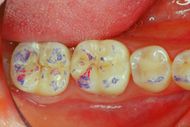

In figure 6a we can see the structures of the crowns in the mouth on which the ceramic will be stratified and which will be covered with Aluvax wax to determine the Functional Neuro Evoked Centric. The decision to incorporate the four molars in the rehabilitation was made because these elements are crucial for occlusal stability but also for mediotrusion as we will see below. The exact mandibular position requires a third anterior point and for this reason, also considering the wear of the incisions and the importance of a normocclusion of the anterior sector, the involvement of the incisors was decisive for Centering the mandible in the optimal position (figure 6b) . Obviously, everything is brought back into articulate with mold waxes on Empress crowns. (figure 6c)

Functional Neuro Gnatologic Detail